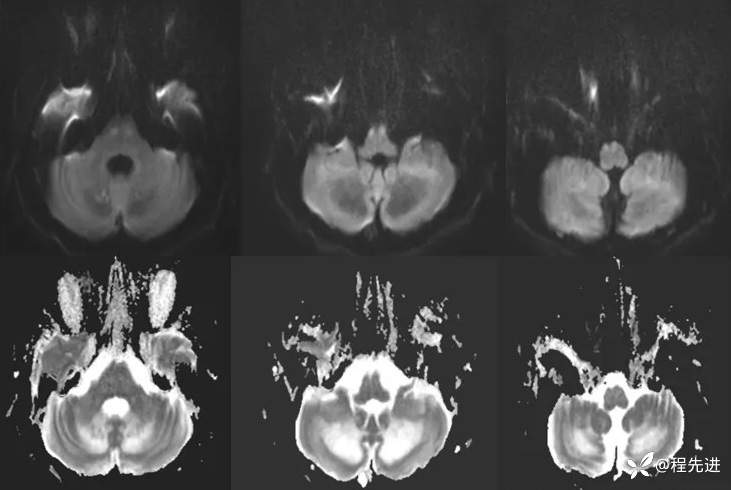

DWI、ADC: